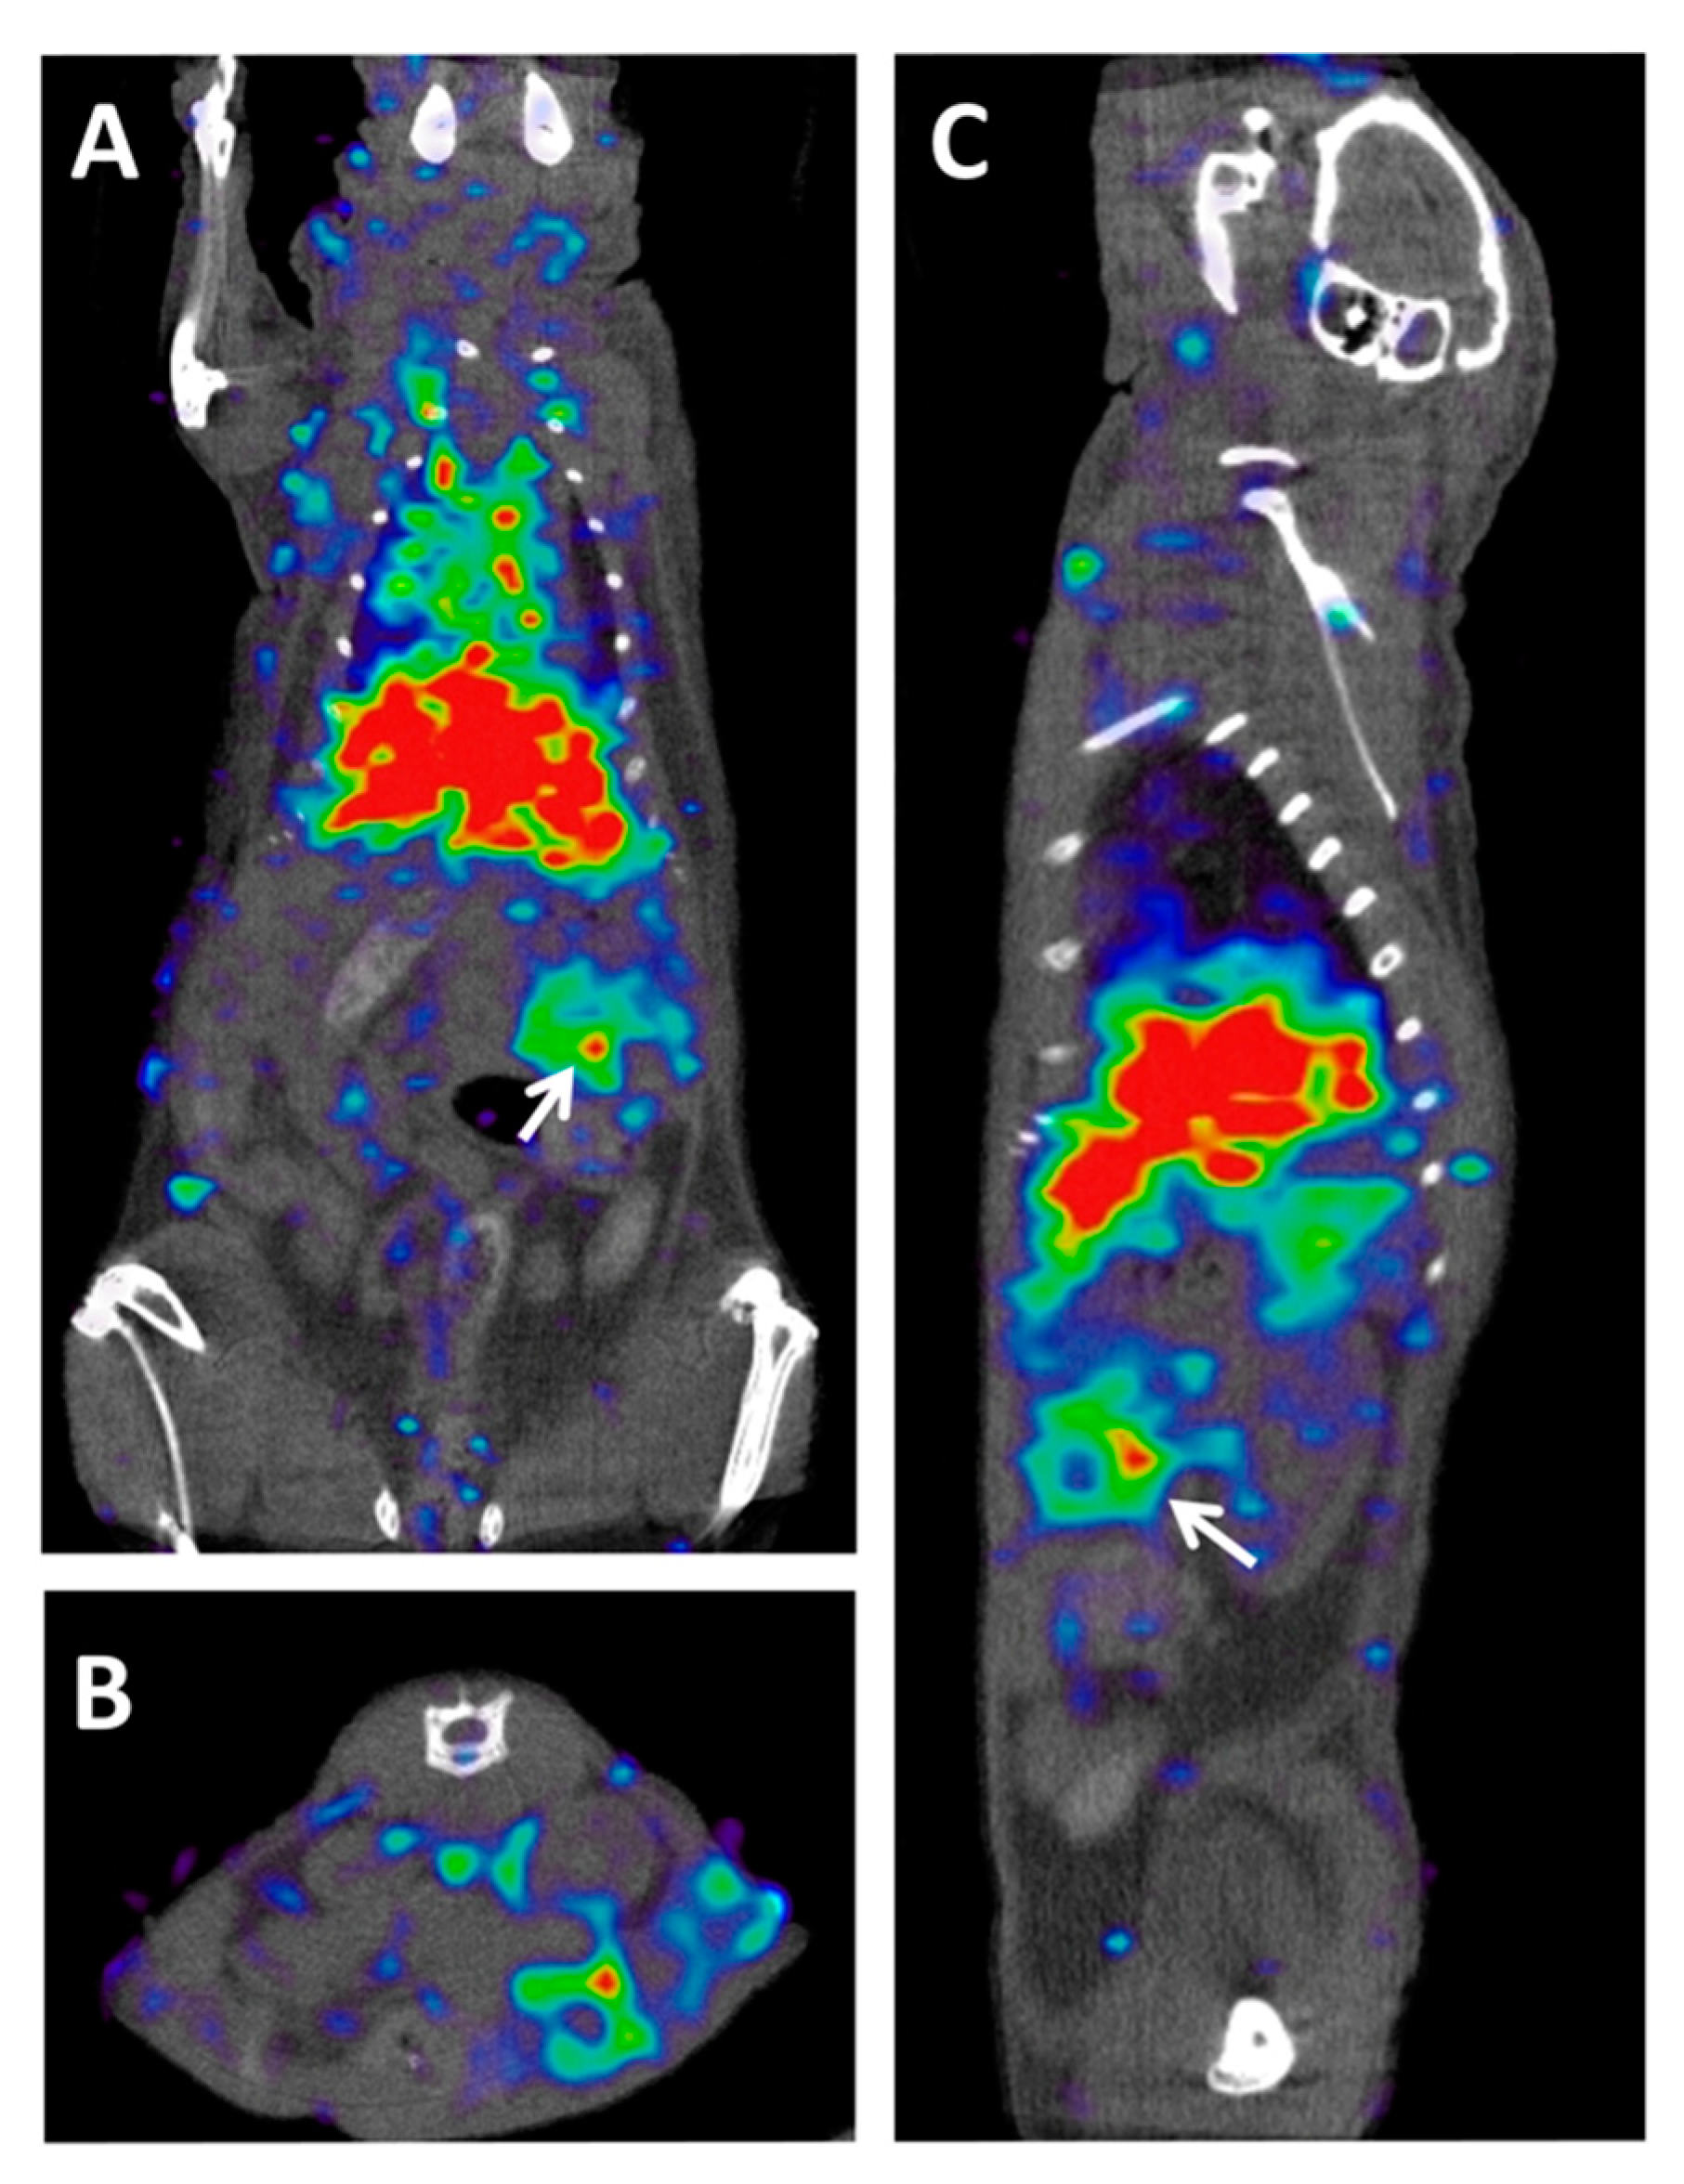

2.4. PET Hybrid Imaging

2.5. Chemotherapy and Radiotherapy Response